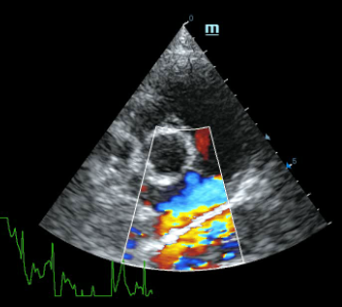

Рисунок 3 Эхокардиография при ДМПП у кошки

Рисунок 4 ДМПП